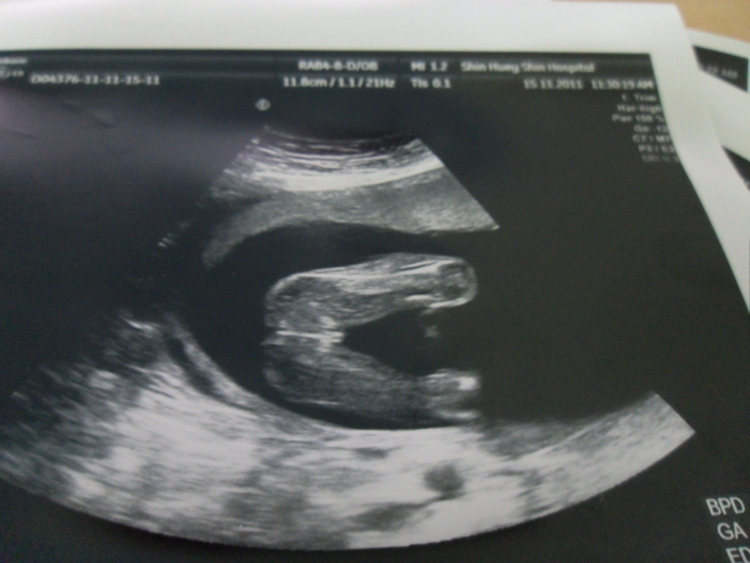

我目前懷孕19週六天..之前去照都因為位置關係所以照不到性別..今天去照超音波醫生說是女生...請問這樣就真的確定是女生了嗎??請有經驗的媽咪幫我看一下..謝謝喔^^

寶寶的腳開很大特徵也很明顯,應該是妹妹沒錯!!

我家小龍女當初雙腳開的角度還不到板水家寶寶的1/2咧!!